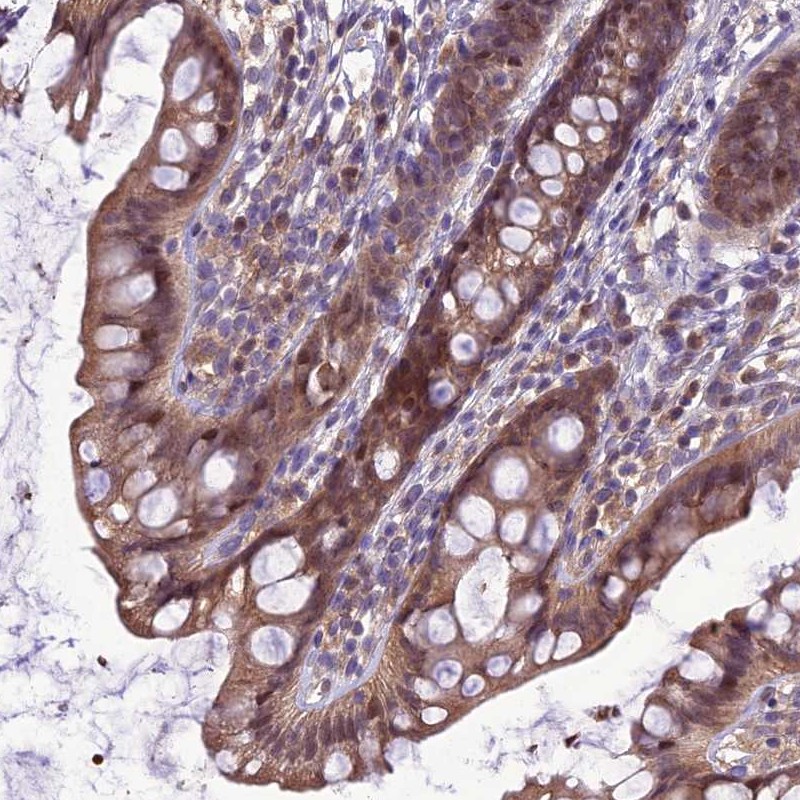

Immunohistochemical staining of human rectum shows moderate cytoplasmic and nuclear positivity in glandular cells.